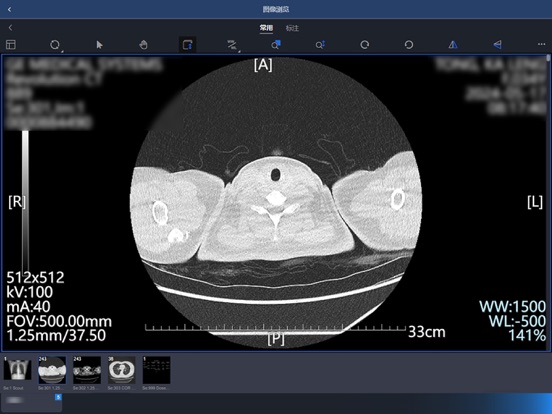

【产品说明】 东软睿影移动办公系统基于云计算和现代互联网技术,实现了各种影像数据和检查报告的云浏览,提供多种图像调整和测量功能,支持远程查看和编辑报告,使得医生可以在任意地点通过移动终端方便快捷的进行远程诊断。 【产品特性】 - 实现了包含放射、超声、内镜、病理、心电等在内的各类影像检查资料的云浏览,可随时随地浏览和诊断; - 采用身份认证机制,多种角色实现用户权限控制; - 支持多种条件查询患者检查信息,并可查看相关检查和申请单; - 多种操作模式,丰富的图像调整和测量功能; - 随时查看和编辑报告,同时支持输入模板,方便医生快速编写报告。 【联系我们】 微信公众号:东软HIT解决方案 客服电话:4006556789-7 官方网站:https://www.neusoft.com/cn1.修复多页报告无法查看的问题 2.增加token有效期自动登录